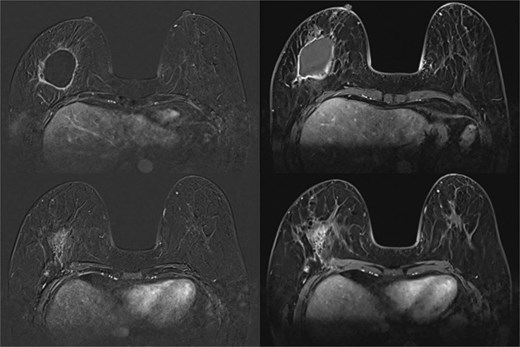

MRI breast showed seroma from excision biopsy and delayed enhancement in the anterior aspect of the collection that may represent residual disease (Fig. 8). She underwent breast conserving surgery to obtain clear margins, and sentinel node biopsy. Wide excision histology showed residual 13 mm invasive carcinoma with clear margins and one lymph node positive on sentinel node biopsy. She subsequently underwent axillary clearance and completion nipple-sparing mastectomy and reconstruction with free deep inferior epigastric perforator (DIEP) flap (Fig. 9). Histology revealed no residual carcinoma and further nodal metastasis. She underwent adjuvant chemotherapy, targeted therapy and radiotherapy. She has remained well 3 years after her surgery and continues to be screened for cancer annually with a MRI for her contralateral breast.

Complications can arise immediately and much later after injection. This patient developed symptoms 9 years after and conventional imaging modalities only identified the presence of silicone. MRI is a more sensitive modality in detecting cancers in patients with siliconomas [4–7]. Cancers can be missed without the appropriate imaging modality in such patients. CESM has been used since 2011 by utilizing the difference in attenuation coefficients of iodine and glandular tissues under low and high energy intermittent exposures to combine and re-create images that eliminate background tissue [7]. The sensitivity of CESM ranges from 93%–100%, with specificity at 63%–88% [8]. A systematic review and meta-analysis by Shahraki et al. showed that CESM has higher specificity, positive predictive value and diagnostic confidence rate than MRI [9]. This is however based on normal breasts without free silicone injection.